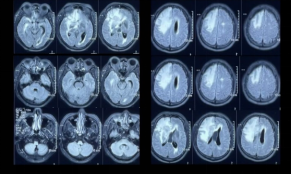

2019年11月,患者因“头痛,无发热、恶心、呕吐,2天好转,反应迟钝,驾车出错”就诊于外院,MRI示双侧大脑半球多发异常信号,右额病灶有占位效应,周围大片水肿(图1),右额病灶环形强化&结节样强化,DWI弥散受限(图2),同期头颅CT示脑实质内散在点状钙化(图3)

图1:双侧大脑半球多发异常信号,右额病灶有占位效应,周围大片水肿